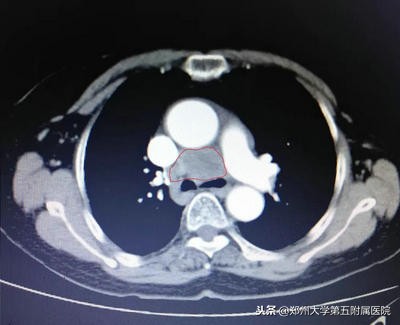

▲ 纵膈占位伽玛刀治疗前和伽玛刀治疗后对比,肿块明显缩小,压迫症状好转

▲ 上图为曾被误诊为炎症的薄壁空洞,下图为增厚的空洞病灶,经穿刺后确诊为肺鳞癌的原发病灶